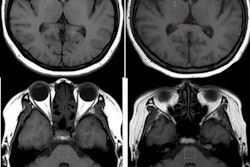

Much of the debate at the September 8 meeting focused on research indicating that gadolinium retention occurs more often with linear-based GBCAs than macrocyclic agents. In its statement, Guerbet noted this distinction and proposed that the evidence supports "precautionary measures primarily with respect to linear agents." The company supported the approach used by the U.S. National Institutes of Health; namely, that linear GBCAs are used only when there is no alternative.

The company also noted that it has already agreed to phase out its linear GBCA, Optimark, and will focus its marketing efforts on its macrocyclic agent, Dotarem. Guerbet said that to date there is "no evidence of gadolinium accumulation in the brain or other tissues after repeated administration" of Dotarem. What's more, the company has recently seen increased demand for macrocyclic GBCAs.